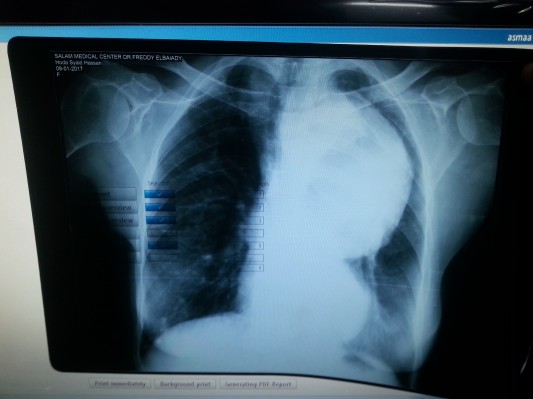

تضخم الشريان الاورطي

هي المريضة ذات الثلاثة و الستين عاما جات تشتكي من ثفو الدم المستمر لمدة شهر دون الوصول الى التشخيص المناسب و لكن بعد عمل اشعة على الصدر و موجات فوق الصوتية على القلب و اشعة مقطعية على الشريان الاورطي وجد انها تعاني من تضخم انشطاري بالشريان الاورطي النازل ، و لكنها ليست الحالة الاولى من نوعها التي يتم تشخيصها للمرة الولى في المركز لذا لاب من معرفة القليل عن هذا المرض

الشريان الاورطي هو اضخم شراييين الجهاز الدوري فهو ينبع من القلب مباشرة و يحمل كمية كبيرة من الدم تحت ضغط عالي جدا و لكن الله سبحانه و تعالى خلقة قادر على استيعاب هذه الكمية الكبيرة من الدم و هذا الضغ العالي فجداره مرن فعن تعرضه لضغ م عالي يتمدد قليلا ثم يعود الى حجمه الطبيعي بعد ان ينخفض ضغط الدم و هذا يحدث بشكل مستمر مع كل دقة قلب و لكن اذا فقد الشريان مرونته عندها تحدث الكارثة فيستمر الشريان الاورطي بالتمدد دون توقف و لا يعود الى حجمه الطبيعي ابدا . من اهم الأسباب التي تفقد الشريان مرونته هي تصلب الشرايين و قد سبق و ذكرنا اسبابها في المقال السابق كالتدخين و السمنة و النام الغذائي الغير متولزن و ارتفاع ضغ الم و ارتفاع نسبة السكر بالدم و ارتفاع الدهون الضارة بالدم ، و بالنسبة لتضخم الشريان الأورطي فمن بين هذه الأسباب يعد ارتفاع ضغط الدم من اقوى الأسباب المؤية له فهو لا يكتفي باحداث هذا الضرر البليغ في الشريان بل و يتسبب في مضاعفات خطيرة قد تؤدي الى الوفاة ، و لأن هذا المرض ينمو بصمت دون احداث اعراض واضحة فهو يصعب تشخيصه . من المضاعفات التي قد تنتج عن هذا المرض هي حدوث انشطار بجدار الشريان المصاب بالتضخم مما قد يؤدي الى هبوط حاد بالدورة الدموية ، فالدم ينحرف عن مساره الطبيعي الى مسار مزيف بين طبقات جدار الشريان و قد يمتد هذا الانشطار ليصيب الابن الاول للشريان الاورطي و هو الشريان التاجي مما يسبب اعراض تشبه الاصابة بجلطة في الشريان التاجي و عندها يصعب تشخيصه و قد يسرع الطبيب باجراء قسطرة قلبية للمريض و التي تكون قاتلة في هذ الحالة ايضا قد يؤدي هذا الانشطار الى انفجار الشريان ، و من المضاعفات التي قد تحدث هي تكوين جلطات بالجزء المتضخم من الشريان و التي قد تتفتت و تنتشر في صورة جليطات صغيرة تحدث انسدادات بالشرايين الصغيرة . و رغم صعوبة المرض الا ان وسائل تشخيصه بسيطة جدا ، فاذا كان هذا التضخم بالجز الصدري من الشريان فعمل اشعة عادية على الصر كافي لتشخيص هذا المرض ، ايضا الموجات فوق الصوتية على القلب لها دور كبير في اكتشاف التضخم الذي يصيب الجز الصدري الصاعد في مراحله الاولى و لكن ادق وسيلة لتشخيص هذا المرض هي عمل اشعة مقطعية على الشريان الاورطي فهي تشخص التضخم و تحدد بدقة مكانه و اذا كان قد اصابه احد المضاعفات السابقة ام لا ، اما اذا كان التضخم في الجزء الباطني من الشريان فتصوير هذا الجزء من الشريان باشعة الدوبلر كافي لتشخيص المرض بكل تفاصيله . العلاج الامثل لعلاج هذا التضخم هو جراحة عاجلة لهذا الجزء المتضخم و لكن هناك طرق احدث و ابسط لعلاجه من خلال القسطرة